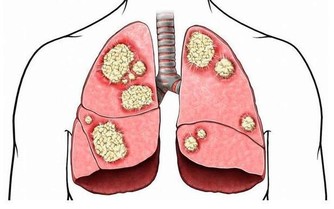

慢性腎功能衰竭,簡稱慢性腎衰,是大家經常說的“尿毒症”,屬於人類十大死因之一。我國慢性腎衰患者中,80%以上的患者發病誘因是高血壓、糖尿病和慢性腎炎。